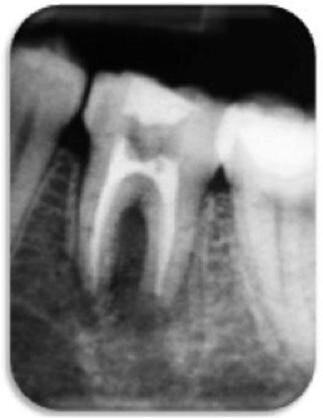

Wykonano końcowe płukanie solą fizjologiczną (3,0 ml), kanał osuszono sterylnymi sączkami, sprawdzanymi na obecność wysięku. Kanały wypełniono ćwiekami gutaperkowymi (2 x F3 i 1 x F4), stosując technikę autodopasowania, pionowego ubicia i uszczelniacz na bazie żywicy epoksydowej (TopSeal, Dentsply), (Ryc. 4 i 5).

Do często podawanych następstw przeszczepu zębów zalicza się ankylozę i resorpcję korzeni.43,44 W opisywanym przypadku klinicznym resorpcję wierzchołkową korzenia dystalnego można powiązać z przerwaniem unaczynienia oraz przewlekłym stanem AP (Ryc. 5).3,8,45